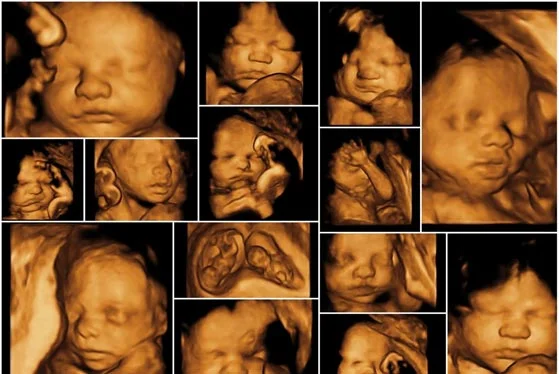

1. Pregnancy (Obstetric) Sonography

Pregnancy ultrasound plays an essential role in monitoring fetal growth, development, and overall maternal health throughout pregnancy. Doctors usually recommend several important scans during different stages of pregnancy, including:

• Early pregnancy scan

• Dating scan

• NT scan

• Anomaly scan

• Growth scan

These scans help identify developmental abnormalities and pregnancy-related complications at an early stage, allowing timely medical management and safer maternal care.